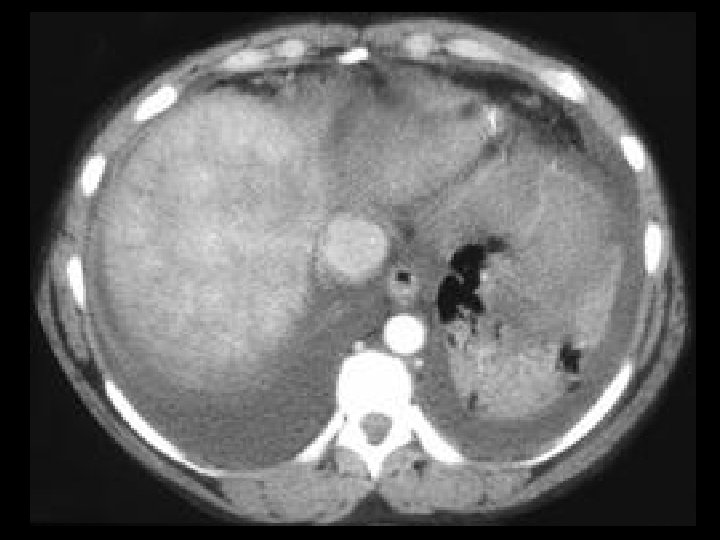

Focal nodular hyperplasia of the liver • Findings: – Single mass in the lateral segment of the left lobe – Intense arterial enhancement EXCEPT for a central “scar” • ddx: – NONE! – This is an Aunt Minnie!